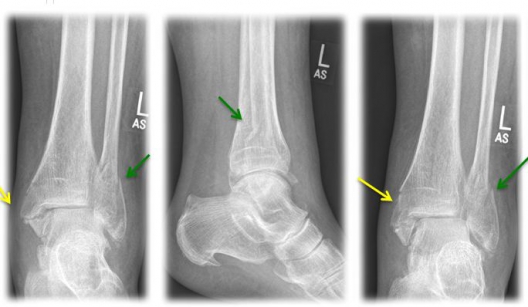

A combined fracture of the inner and outer ankle is referred to as a "bimalleolar ankle fracture" (see Fig. 3). If, in addition, the posterior lower tibia edge (=Volkmann's triangle) is broken, it is called "trimalleolar ankle fracture".

Fig. 3) "Bimalleolar ankle joint fracture" left x-rayed in 3 planes (a.p., lateral, internal rotation) with an internal ankle fracture (yellow arrow) and a spiral external ankle fracture (green arrow)